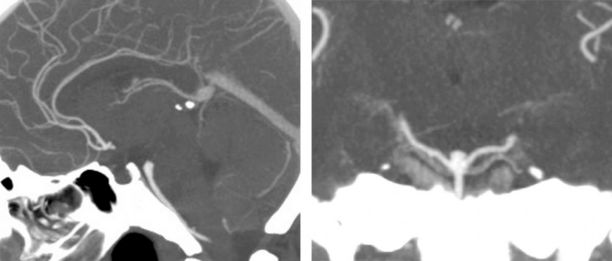

图1:一个低位基底动脉分叉部动脉瘤,瘤颈位于鞍背下方1cm,可经颞下入路显露。

应仔细考虑至关重要的Labbé静脉的位置,因为前置型静脉将限制或阻碍安全使用颞下手术通路。